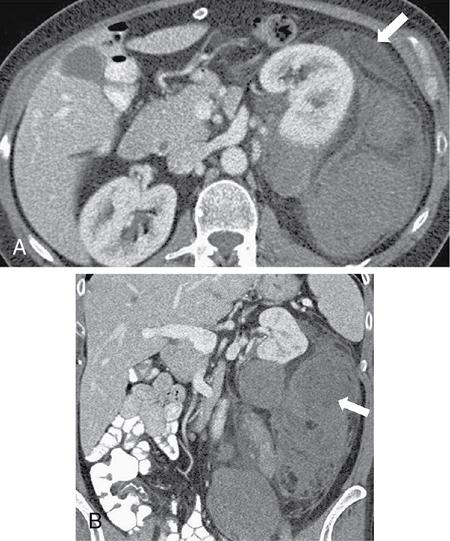

Image

Fig. 10.17.1.9 Contrast-enhanced axial (A, B) and sagittal CT (C) sections in a case of a perinephric haematoma (asterisks in A and B). It extends into the retromesenteric and retrorenal planes by means of bridging septae which traverse the perirenal space (blue arrow in A). Inferiorly, it extends along the combined interfascial plane into the pelvis (blue arrow in C).